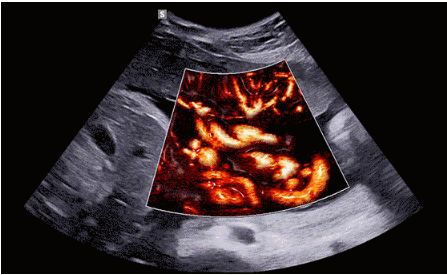

3D/4D成像方面,Hera i 10通過結(jié)合先進(jìn)的圖像渲染技術(shù),著重加強(qiáng)了邊緣和小結(jié)構(gòu)的可視化能力。